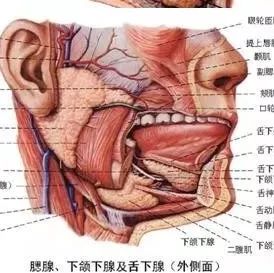

腮腺详细解剖及疾病诊断技巧 医学界影像诊断与介入频道 · 公众号 · 医学 · 7 年前 · |